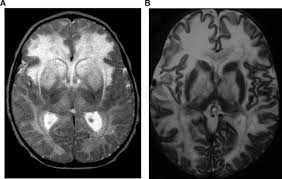

Non Genetic Therapeutic Approaches To Canavan Disease Journal Of The Neurological Sciences

Pdf Lithium Citrate For Canavan Disease